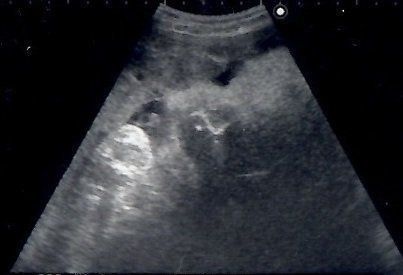

妊娠9週目のエコー写真 胎児の姿が見えてきた!

エコー画像で頭と胴体が分かれた人間らしい姿を見て、いよいよ妊娠したという実感がわいてきました。それと同時に、このまま無事に育ってくれるのだろうかという不安で毎日祈るような気持ちでいました。いまだにこの画像を見るたびに、この時の不安でたまらなかった自分の気持ち、そして生命の神秘を目の当たりにしたときの厳粛な気持ちを思い出し、胸がいっぱいになります。